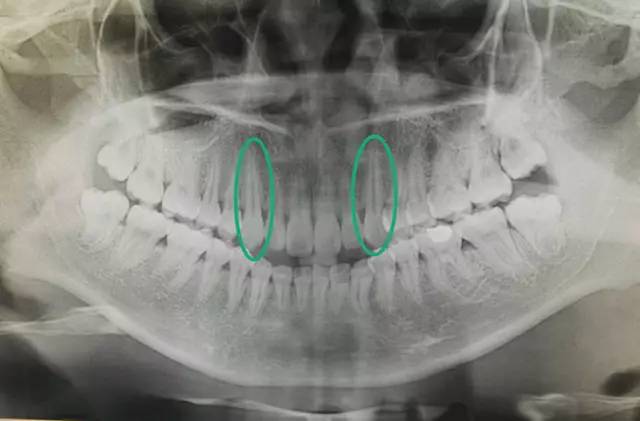

从图中可以看出,尖牙长出的时间是在侧切牙和第一前磨牙之后的

如图,尖牙是所有牙齿当中牙根最长的